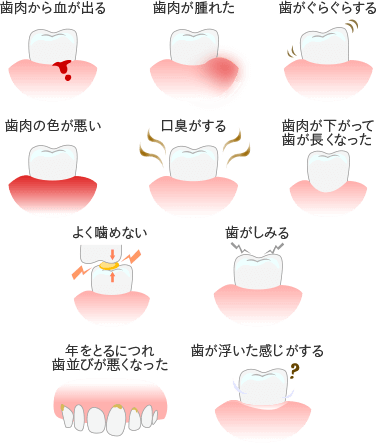

歯周病とはどんな病気かご存知でしょうか?歯周病は歯を失う原因の第一位とされていて、近年では実はむし歯よりも深刻な病気として知られています。

歯周病は初期症状がほとんどないことが特徴で、気がついた時には重症化していることも少なくない恐ろしい病気です。最悪の場合、歯が抜け落ちてしまう可能性もあるため、歯周病は早期発見・早期治療が最も重要となります。

以下のような症状に心当たりのある方は、歯周病の可能性があります。どんなに些細な症状でも、気になる症状がございましたらお気軽にご相談ください。